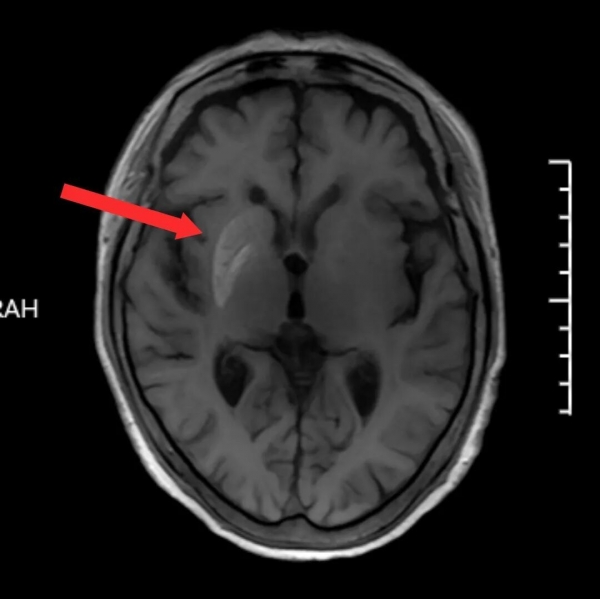

头颅磁共振(MRI)检查显示一个关键线索,在影像上可以看到,孙奶奶右侧大脑豆状核区域显示出异常高信号,而在其他序列中该区域并无明显异常。这一特异性影像表现,引起了放射科主任陈子虎的高度重视。

他迅速组织团队集体阅片讨论。由于患者有长期糖尿病史、血糖控制不佳,虽未出现酮症酸中毒等急性并发症,但结合其症状以及MRI上特征性表现,应重点考虑与代谢相关的罕见疾病。

"该病多见于血糖控制不良的老年糖尿病患者,尤其是女性。其典型影像学标志也与患者影像表现高度吻合。"通过老年医学科与放射科的多学科会诊,胡安定医疗团队逐步排除了脑卒中、肿瘤、颅内感染、免疫性脑炎等常见病因,最终锁定病因--非酮症高血糖性偏侧舞蹈症。该病的根本机制在于长期高血糖对大脑基底节区神经细胞代谢的影响。